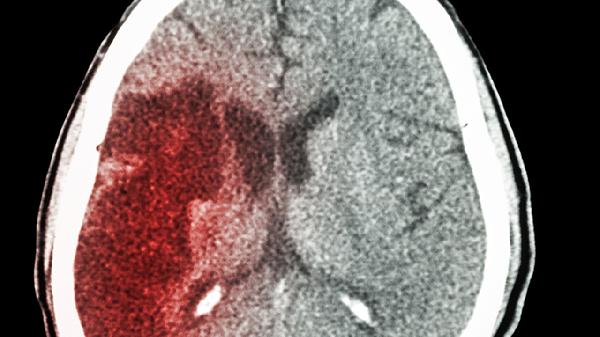

50岁女子突发脑溢血离世,医生告诫:夏天再热,也不要做这5件事

突发剧烈头痛、单侧肢体麻木、言语含糊等症状出现时,应立即平卧休息并呼叫急救。黄金抢.救时间在发病后3小时内。